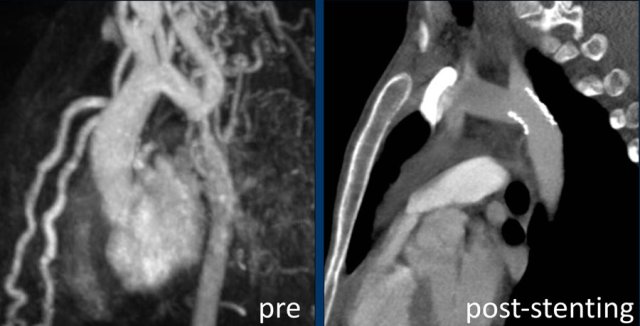

Intravascular stent therapy is considered a primary therapeutic option for most adults and adolescents with coarctation of the aorta (refence).

Image: intravascular stent in good position.

MRA-image of the same patient pre-stenting.

CTA-image post-stenting.